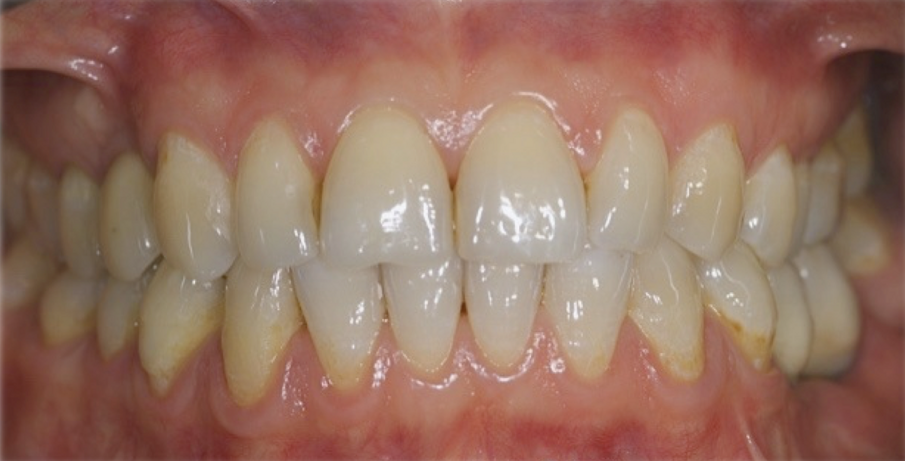

Una paziente di 35 anni si presentò alla nostra attenzione per risolvere un edentulismo parziale nella zona mandibolare inferiore sinistra conseguente all’estrazione traumatica degli elementi 35 e 36 in età scolare (Fig. 1). La paziente all’esame obbiettivo dimostrava un ottima igiene orale con un indice di placca del 7% e un indice di sanguinamento del 5%. L’esame clinico della zona traumatizzata evidenziava una lesione di terza classe di Seibert6 laddove il deficit osseo era caratterizzato da una deficienza nei tessuti duri e molli sia in senso orizzontale che in senso verticale. Risultava significativa anche la scarsa quantità di gengiva cheratinizzata a ricoprire la cresta residua, quantificabile in una banda larga non più di 2 mm (Fig. 2). Una volta eseguita la terapia causale atta a rimuovere il biofilm presente e a preparare la paziente per l’intervento, si procedette a eseguire un esame Cone Beam per approfondire la conoscenza dell’anatomia locale e procedere con un piano di trattamento adeguato alla soluzione di questa problematica.

Nella rx si vedono i due impianti con le viti di guarigione ad integrazione avvenuta. In figura 16 si nota l’ottimo aspetto dei tessuti peri-implantari con una adeguata quantità e qualità di gengiva cheratinizzata e le susseguenti corone in metallo ceramica successivamente cementate su due perni moncone in titanio fresati in laboratorio. Nelle foto successive si possono evidenziare le differenze dalla situazione iniziale (Fig. 17) a quella finale, in questo caso una foto di follow up a 48 mesi dalla finalizzazione del caso (Fig. 18). La rx a quattro anni dalla finalizzazione protesica evidenzia una situazione di perfetta stabilità, una cresta ossea ben mineralizzata ed un livello osseo inalterato dal momento della consegna del manufatto protesico definitivo (Fig. 19).